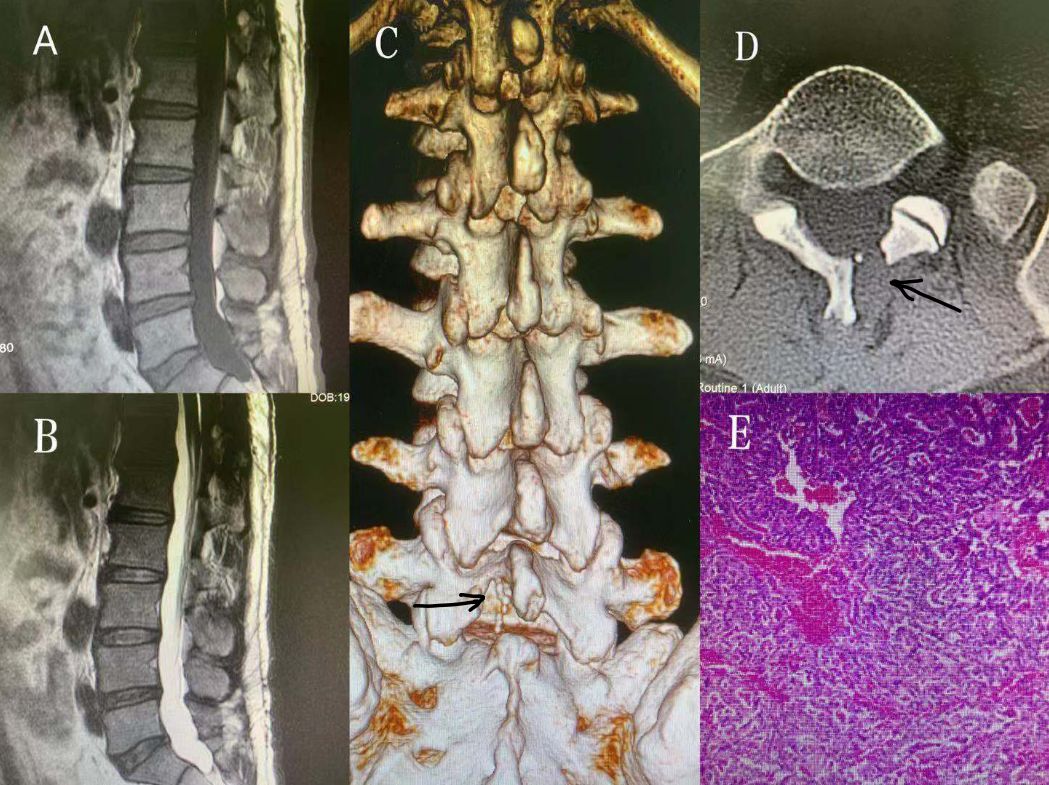

椎管内马尾终丝副神经节瘤二例

表现为颅高压症状的腰椎管内副神经节瘤一例脊柱脊髓系列九浙二神外

表现为颅高压症状的腰椎管内副神经节瘤一例(脊柱脊髓系列九)---浙二